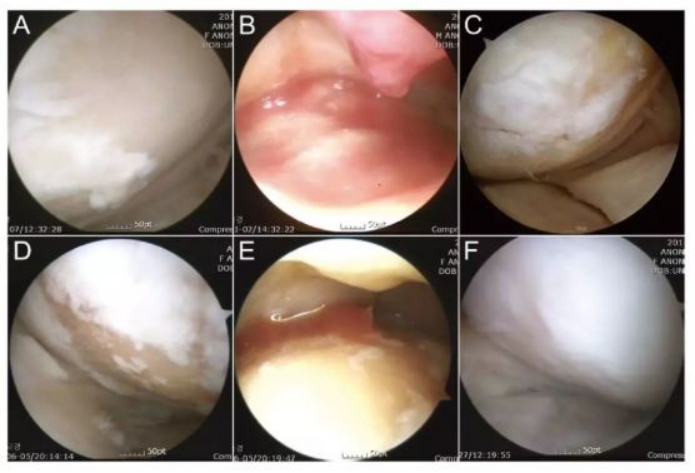

下图可以看出从左往右随着间充质干细胞治疗的变化软骨逐渐得到修复

image.png